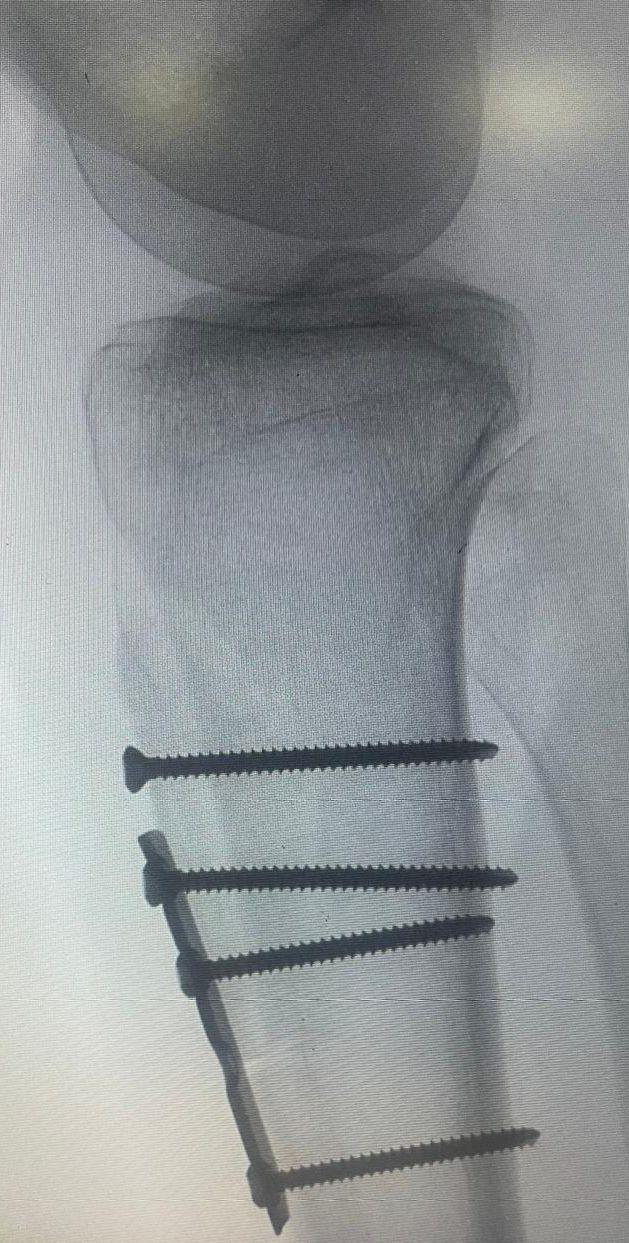

حيث تقرر اجراء عملية قص جذر وتر عظمة الرضفة وتغيير مسارها وتثبيتها جراحياً، إلى جانب إجراء تثبيت جانبي لنفس العظمة باستخدام وتر العضلة الخلفية بتقنية المنظار الجراحي وتتمتع المريضة بصحة جيدة بعد توفيق الله وتتابع التأهيل بمركز العلاج الطبيعي بالمجمع للوصول الى افضل النتائج.

وأكد ” الحليبي ” أن هذه الجراحة تُعد من العمليات النادرة في مجال جراحة العظام، حيث تتطلب خبرة ومهارة عاليتين، موضحاً أن مثل هذه الحالات كانت تُحول سابقاً إلى مراكز طبية خارج المنطقة ، مسلطا الضوء على التطور الكبير الذي حققه مجمع الدمام الطبي في مجال جراحة العظام. و دليلاً على التقدم الملحوظ الذي احرزه في علاج الحالات النادرة والمعقدة، وذلك بالاعتماد على أحدث التقنيات الطبية وتوفير فرق طبية مؤهلة للتعامل مع أدق العمليات الجراحية، مما يُسهم في الارتقاء بمستوى الخدمات الصحية المقدمة للأهالي في المنطقة الشرقية.